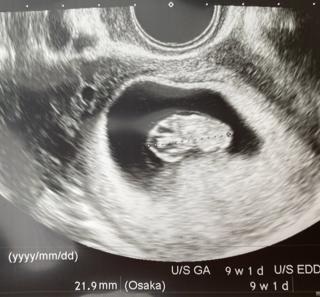

思ったより大きくて、

今日で8週3日だけど、

9週1日の大きさだねって言われました。

だから、予定日が早くなるかも!と思ったけど、

予定日の誤差は、1週間以内なら最終月経からの計算と変えないガイドラインみたいなので、そのまま10月5日となりました。